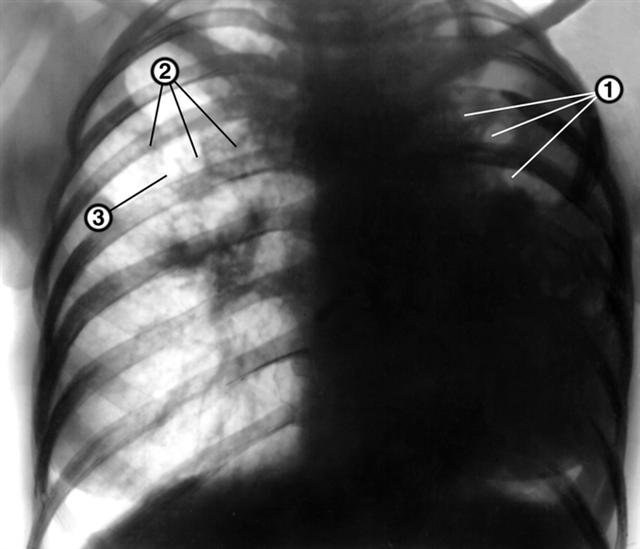

Рис. 13а). Рентгенограмма органов грудной клетки в прямой проекции больной фиброзно-кавернозным туберкулезом правого легкого и левосторонней казеозной пневмонией: левое легкое уменьшено в объеме, диффузно затенено, в верхних его отделах определяются множественные полости распада (1); правое легкое увеличено в объеме, в средних его отделах определяются очаги отсева (2), на уровне второго межреберного промежутка — каверна (3); тень средостения смещена влево. |